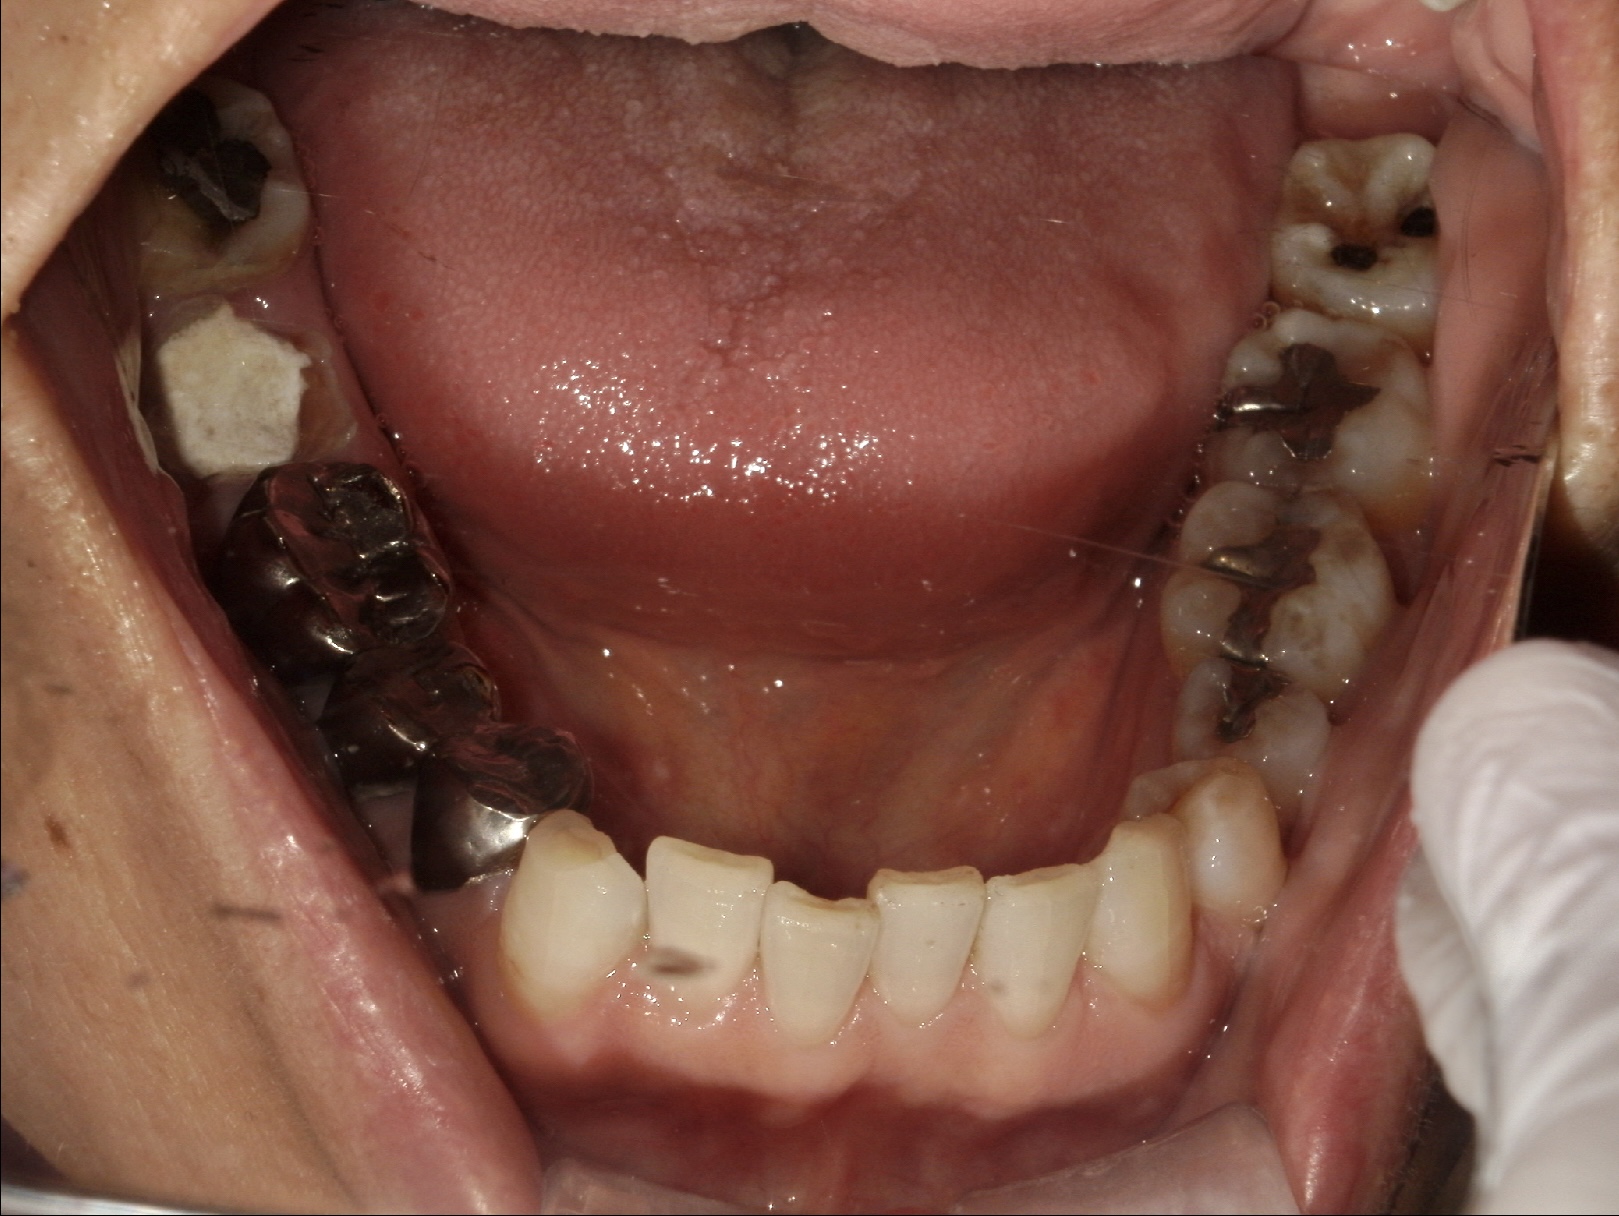

| 主訴 | 右下欠けたところがある。その他虫歯を治療したい |

| 年齢 | 60代女性 |

| 治療内容 | スクリューポスト不適合で、根尖病巣も大きく残すことが難しいため抜歯しインプラント治療へ。 歯槽骨の量が不足している場合に、人工骨や自家骨を移植し、特殊な膜で覆うことで骨の再生を促し、インプラントを埋入できるようにするGBRという治療法も併用。 |

| 抜歯部位 | 右下7 |